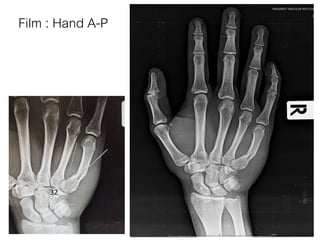

Film : Hand A-P

32